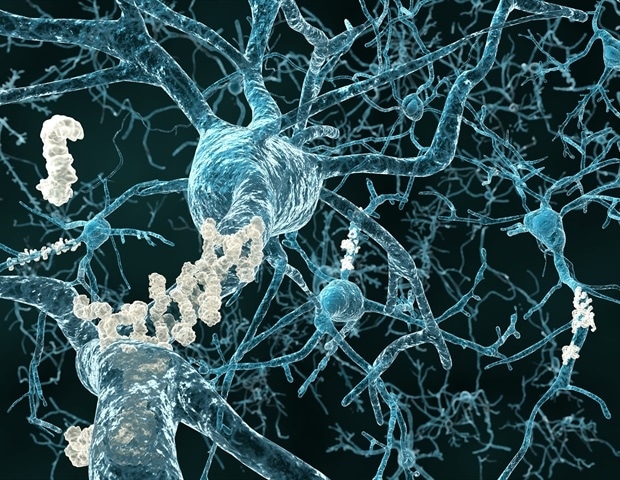

חוסר איזון של חלבון שמגביר את רגישות תאי המוח עשוי להסביר מדוע אנשים עם מחלת אלצהיימר (AD) שחווים גם התקפים